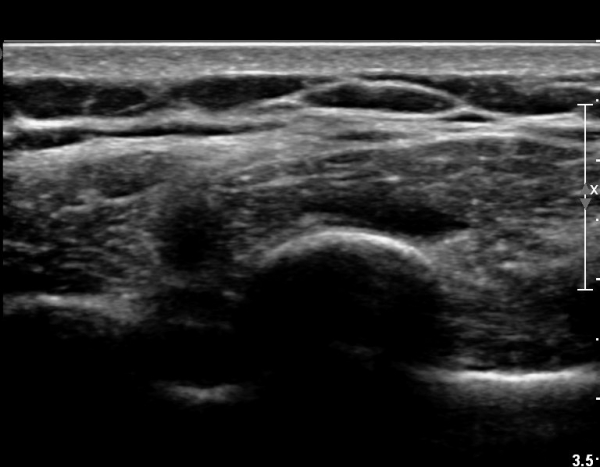

8¹øÂ° °¥ºñ»À Á¾´Ü¸é°Ë»ç»ó °¥ºñ»À Ç¥ÃþÀ¸·Î Àú¿¡ÄÚ ºÎÁ¾°ú °¥ºñ»À Ç¥Ãþ¿¡ ÀÖ´Â

±Ù¼¶À¯µéÀÌ Ç¥ÃþÀ¸·Î ¹Ð·ÁÀÖ´Â °ÍÀÌ °üÂûµÇ°í(»çÁø 1, 2) °¥ºñ»À ÇÇÁú°ñ ¿¬¼Ó¼º

´ÜÀýÀÌ ÀǽɵȴÙ(»çÁø 2).